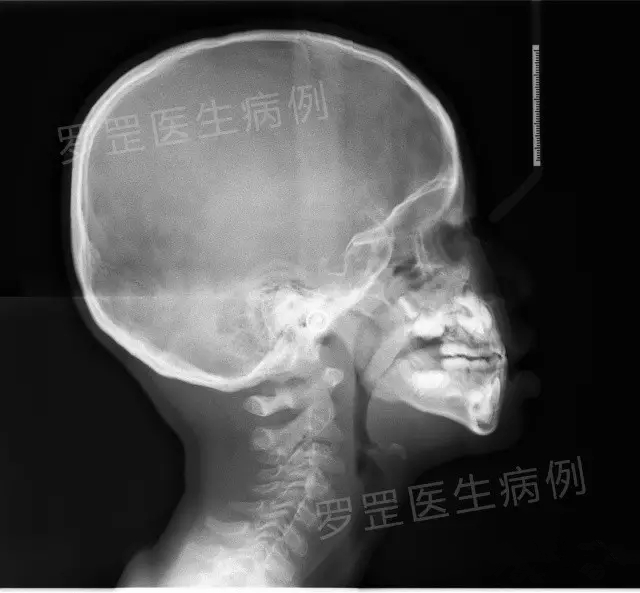

2.拍片

(头颅侧位片)

如果家长选择了某种形式,医森初诊当天会安排助手给小朋友拍摄口腔全景片&头颅侧位片,可以更加准确了解小朋友牙齿生长发育情况及骨骼发展情况,以便更好制定正畸方案。